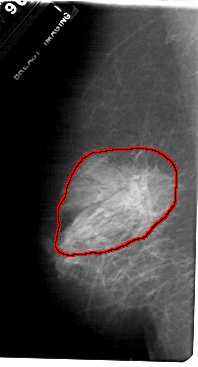

FILE: A_1720_1.LEFT_MLO.OVERLAY

TOTAL_ABNORMALITIES 1

ABNORMALITY 1

LESION_TYPE MASS SHAPE ARCHITECTURAL_DISTORTION MARGINS SPICULATED

ASSESSMENT 2

SUBTLETY 5

PATHOLOGY BENIGN_WITHOUT_CALLBACK

TOTAL_OUTLINES 1

BOUNDARY